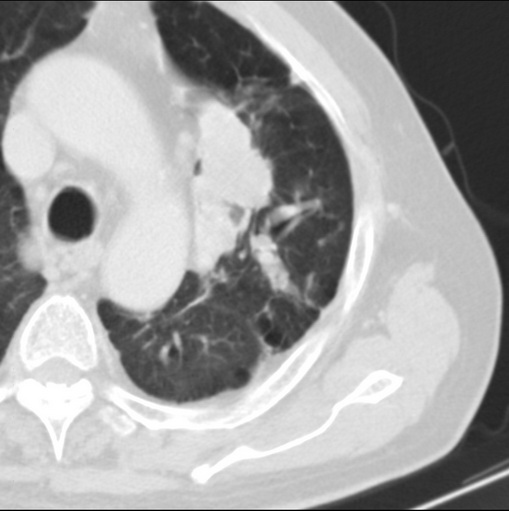

男性患者 81岁 咳嗽 咳痰 咯血

肿块贴近左肺门,包绕左上肺动脉,形态不规则。肿块增强扫描中度强化。纵膈内主动脉弓左旁间隙、气管隆突前、下间隙见多枚淋巴结影。综上考虑左侧中央型肺癌可能性大。图片没有完整上传,尤其是左肺上叶支气管分支层面没有上传,因此不好判断是叶支气管中断还是段支气管中断。另外,下图红色部分所示是“黏液支气管征”吗?